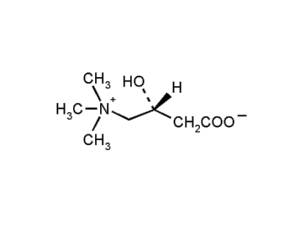

Для существования и функционирования любой живой клетки необходима энергия. L-карнитин участвует в обмене веществ как переносчик жирных кислот в митохондрии, где происходит превращение жиров в энергетическое «топливо» для организма.

В состав лекарства Элькар входит аминокислота L-карнитин (левокарнитин), которая еще называется витамином роста или витамином ВТ, она близка по структуре с витаминами группы В.

Основным действующим веществом препарата Элькар является Левокарнитин (его еще называют L-карнитин) — это аминокислота, полученная синтетическим способом и аналогичная по своему химическому составу аминокислоте, которая синтезируется в организме и принимает участие в метаболических процессах, стимуляции выработки некоторых ферментов, участвует в липидном и белковом обмене, отвечает за снабжение тканей и органов энергией.

Основным действующим веществом препарата Элькар является Левокарнитин (его еще называют L-карнитин) — это аминокислота, полученная синтетическим способом и аналогичная по своему химическому составу аминокислоте, которая синтезируется в организме и принимает участие в метаболических процессах, стимуляции выработки некоторых ферментов, участвует в липидном и белковом обмене, отвечает за снабжение тканей и органов энергией.

По химической структуре аминокислота Левокарнитин схожа с витаминами группы В, ее даже относят к витаминоподобным веществам, за ней закрепились названия витамин ВТ и витамин роста.

Аминокислота Левокарнитин синтезируется в почках и печени и присутствует почти во всех тканях и органах человеческого организма, достигая самой высокой концентрации в печени, в мышечной ткани и в тканях головного мозга. Для синтеза указанной аминокислоты необходимо участие многих витаминов и микроэлементов.

Аминокислота Левокарнитин синтезируется в почках и печени и присутствует почти во всех тканях и органах человеческого организма, достигая самой высокой концентрации в печени, в мышечной ткани и в тканях головного мозга. Для синтеза указанной аминокислоты необходимо участие многих витаминов и микроэлементов.